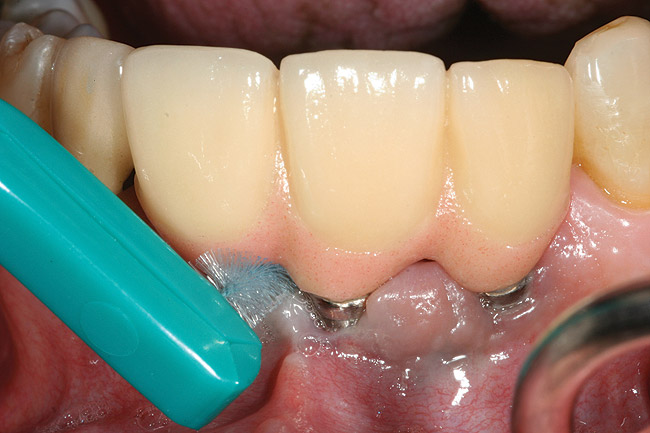

Conventional periodontal therapy should be instituted if inflammation develops around an implant. Therapy should include efforts to improve patient oral hygiene, using similar methods as around natural teeth (Figure 4A and Figure 4B). Lang et al suggested a novel, systematic stepwise approach for the prevention and treatment of peri-implant diseases referred to as the cumulative interceptive supportive therapy (CIST) protocol46 (Table 4). This system is based on periodic monitoring with implementation of treatment as thresholds for a particular condition are met. The first step is protocol A, then B and, if conditions continue to worsen, the case may require more advanced treatment, which may include comanagement with a specialist who has implant training to execute protocol C, and finally D.20 Protocol A is used to control inflammation in peri-implant mucositis, that is, implants with minimal increase in pocket depth, slight (+) bleeding on probing, marginal erythema, plaque, and/or calculus. The therapeutic endpoint is to resolve inflammation with cautious mechanical debridement (using plastic curettes and rubber cup prophylaxis), twice-daily swabbing with 0.12% chlorhexidine, and a review of home care and patient motivation. Protocol B is initiated for conditions that exhibit similar mucositis features but with deeper pocket depths (4 mm to 5 mm); however, there is still no loss of supporting bone. The treatment should include the therapies of protocol (A), plus locally delivered antibiotic (minocycline microspheres, doxycycline gel) at the infected implant site(s). Recent studies have shown the use of minocycline microspheres may be beneficial in treatment of peri-implant mucositis and peri-implantitis.46 Management of early peri-implantitis, protocol C, requires a more robust approach and is used in conditions with evidence of osseointegrated bone loss of < 2 mm and pocket depths > 5 mm. The strategy should comprise the modalities for protocols A and B with the addition of systemic antibiotic therapy (metronidazole 250 mg t.i.d. for 7 days or amoxicillin 500 mg t.i.d. for 10 days).

Figure 4a  Use of a proxi-brush and large-diameter floss to perform plaque control around an implant-supported/retained prosthesis

Figure 4a

Figure 4b  Use of a proxi-brush and large-diameter floss to perform plaque control around an implant-supported/retained prosthesis

Figure 4b